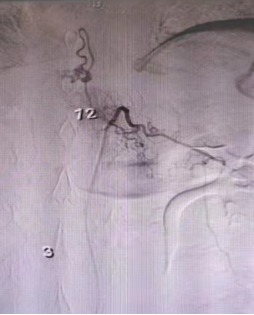

脊髓造影可见胸12腰1节段左侧硬脊膜动静脉瘘

术中造影可见瘘口